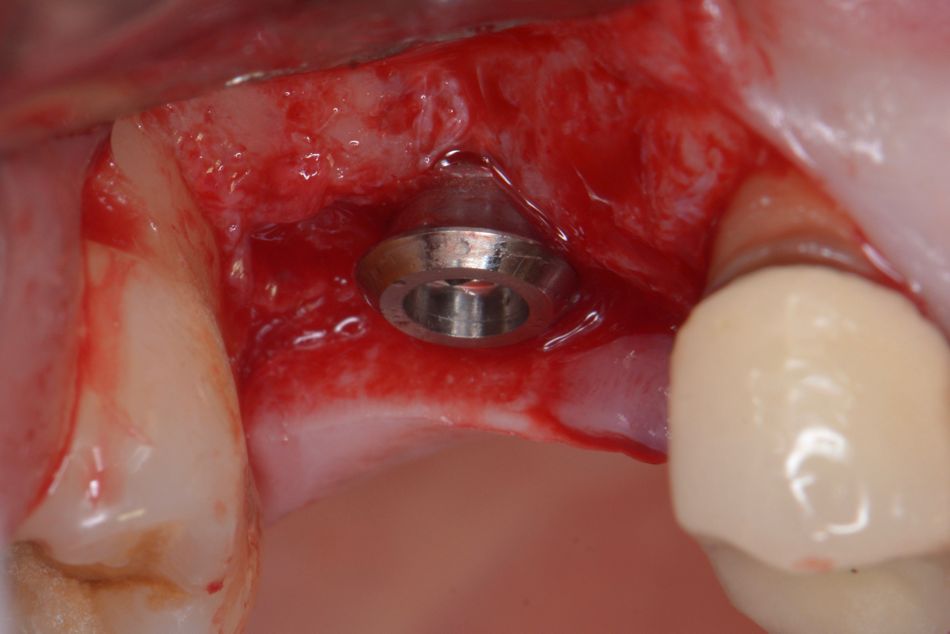

The Straumann®  TLX implant was placed with a surgical ratchet with a torque value >35 Ncm, and optimal primary stability was achieved (Figs. 10-12).

Single stitches with nylon 5-0 were placed around the implant. Analgesics were prescribed post-operatively, and a control and suture removal was planned one week later. The follow-up appointments were scheduled for 30- and 60-days post-surgery (Figs. 19,20).